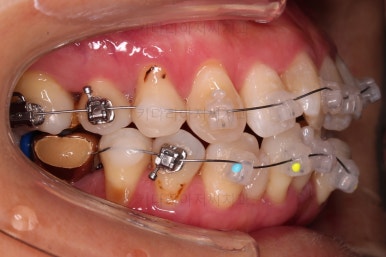

적절한 시점에 유치를 뽑아내고 남은 공간을 줄여나갑니다.

아래쪽 임플란트는 움직이지 않기 때문에 해당 치아를 기준으로 다른 치아를 모두 셋팅해야 하는 매우 난이도 높은 치료가 진행되었습니다.

발치 공간 앞뒤 치열을 당겨주어 공간을 줄여 나갑니다.

자연스레 입은 들어가게 될 것이고요.

충분히 당겨준 뒤, 얼굴모습을 보고 의논을 합니다.

현재 남은 공간-어느 정도 더 들어갈지 - 지금 현재모습에 만족하시는지 등 의견교환을 하며 입을 더 넣을지 더 안넣도록 할지 결정을 합니다.

임플란트는 크기가 작았으므로 교합을 위해서는 어쩔 수 없이 해당 부위에 틈이 남을 수 밖에 없었고요.

남은 틈은 임플란트 상부 보철을 재제작하면서 조절을 하기로 했습니다.